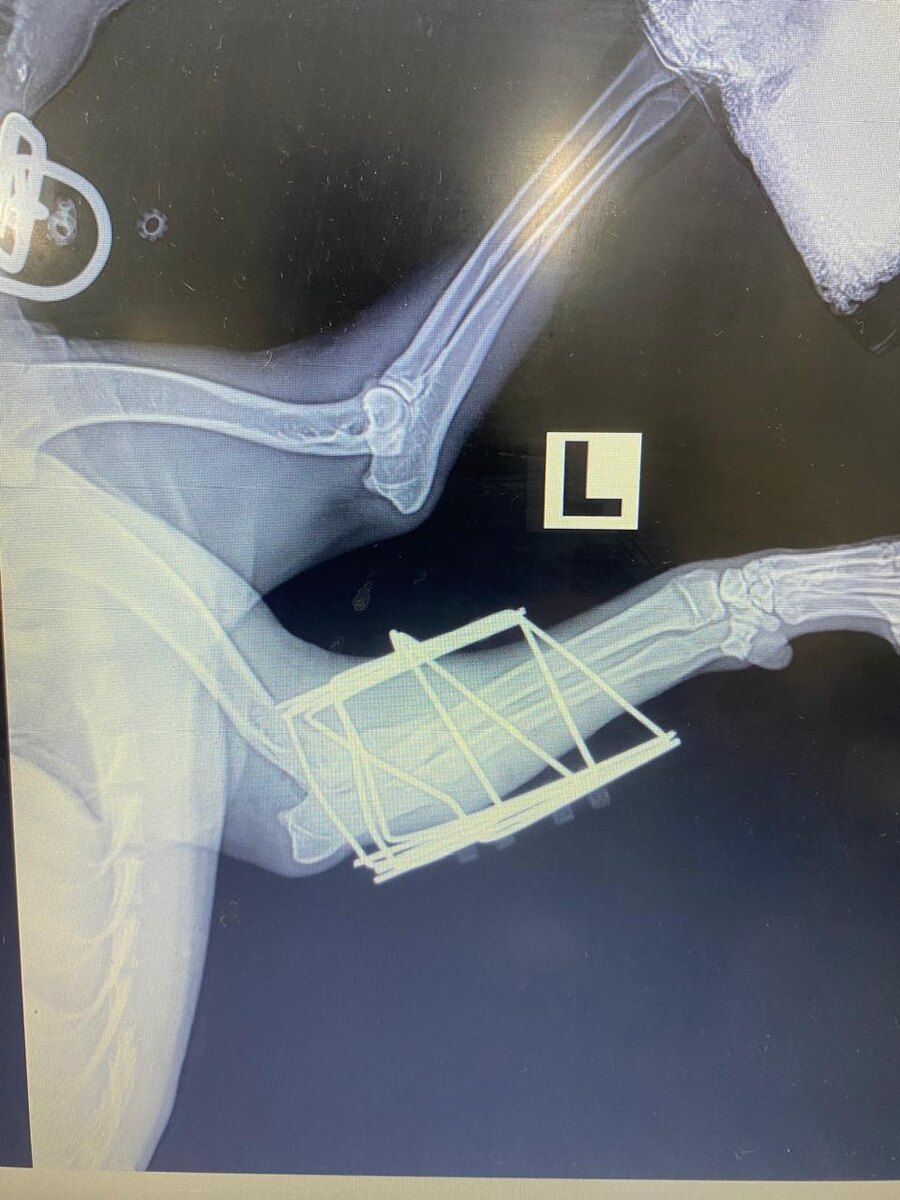

Зооволонтёры Усть-Лабинска благодарят неравнодушных людей за помощь пострадавшей собаке. Оперативно собрали деньги на операцию в ветклинике Краснодара. К перелому передней лапы добавились и другие проблемы со здоровьем, поэтому собаку пришлось сразу стерилизовать. Сейчас Линда находится на временной передержке в Усть-Лабинске, где о ней заботится хозяйка домашнего приюта Наталья. 🚀 Подписаться | Прислать новость

К перелому передней лапы добавились и другие проблемы со здоровьем, поэтому собаку пришлось сразу стерилизовать.